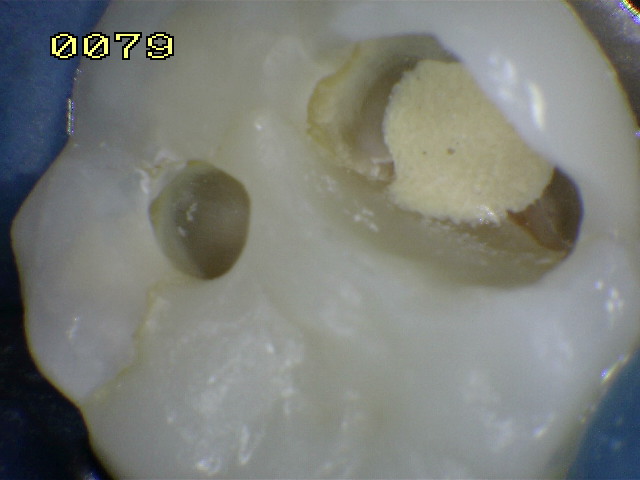

La flecha

amarilla indica un posible cuarto conducto. |